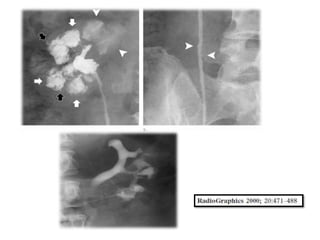

histerosalpingografía se indica. Prácticamente todos las

pacientes tendrán hallazgos anormales.

Varios criterios diagnósticos se han descrito: los ganglios

linfáticos calcificados o calcificaciones pequeñas en las

regiones anexiales, obstrucción del tubo entre el istmo

y la ampolla, adherencias endometriales y en las

trompas sin antecedentes de legrado o aborto.